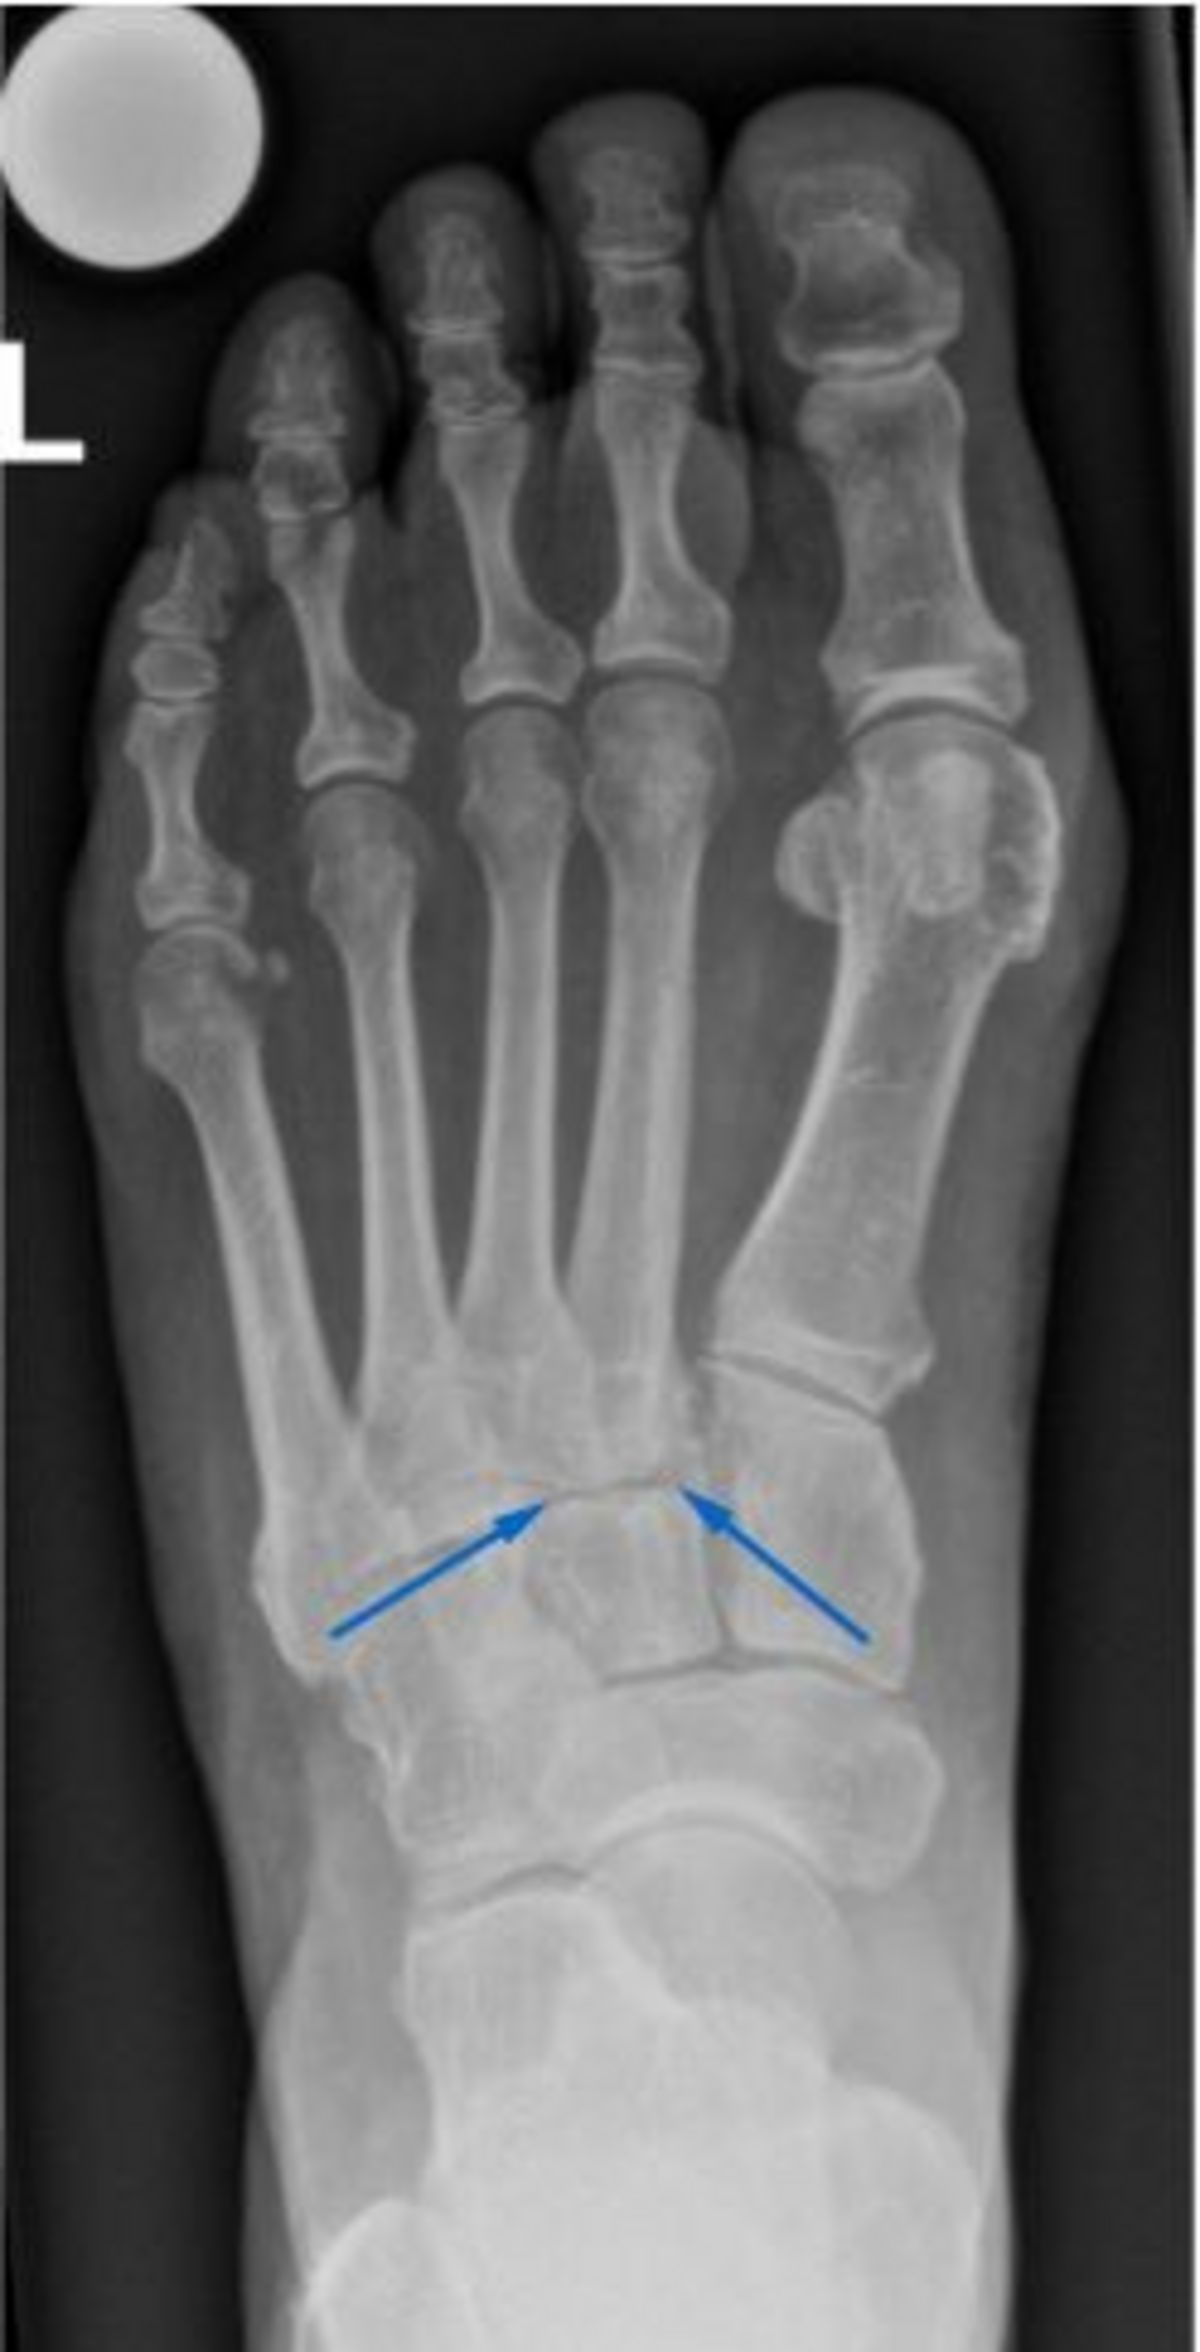

Bild: Universitätsklinik Balgrist

Röntgenbilder sind zur Diagnosestellung hilfreich. Zum einen zeigen sie meist bereits die Arthrose der Gelenke, zum anderen kann ihre Stabilität beurteilt werden. Aufgrund der Form des Fussgewölbes sind Röntgenbilder mehrerer Ebenen notwendig, um eine zuverlässige Aussage treffen zu können. Unter Umständen ist zusätzlich eine Magnetresonanztomographie (MRT bzw. engl. MRI für magnetic resonance imaging) nötig, um das genaue Ausmass der Arthrose und Verletzung des Mittelfusses bestimmen zu können.